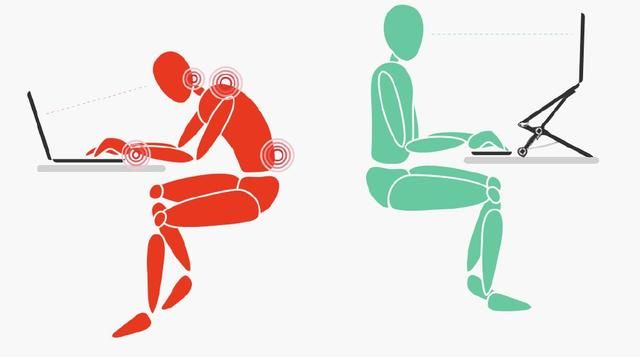

不当姿势

这是最常见的危险因素,例如——

人平躺时,腰椎受力最小,大约25公斤;直立时,腰椎受力约100公斤;坐着时,上半身直立状态下腰椎受力约140公斤。上半身前倾会使腰椎受力骤增,站着身体往前倾时,腰椎受力变为150公斤;坐着身体往前倾时,腰椎受力增大到近200公斤。

腰部受寒,健身卧推,久坐,通宵打麻将,玩手机,过度负重,弯腰……都容易导致腰椎间盘突出。

柜台迎宾等服务行业从业者、重体力劳动者、伏案办公的白领一族等,都是腰椎间盘突出的高发人群。